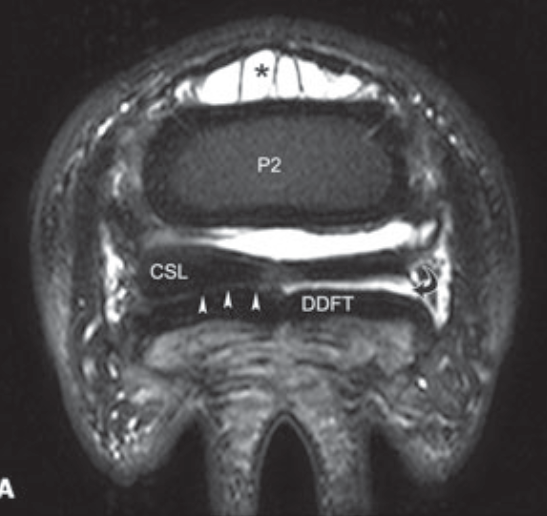

What structure is the asterik in?

Dorsal pouch of the distal interphangeal joint

What structure separates the navicular bursa and the distal interphalangeal joint?

Distal sesamoidean impar ligament